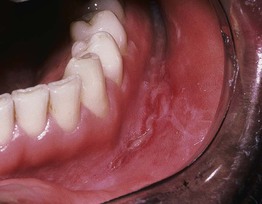

– Contiguous lesions are seen in the mouth, perioral, anogenital region, and peristomal areas with clinical presentations varying from fissures to cobblestoning to swelling (Figs. 78.10 and 78.11).

Fig. 78.10 Crohn's disease. Linear ulceration of the mandibular vestibule: the classic oral manifestation of this disease. Courtesy, Charles Camisa, MD.